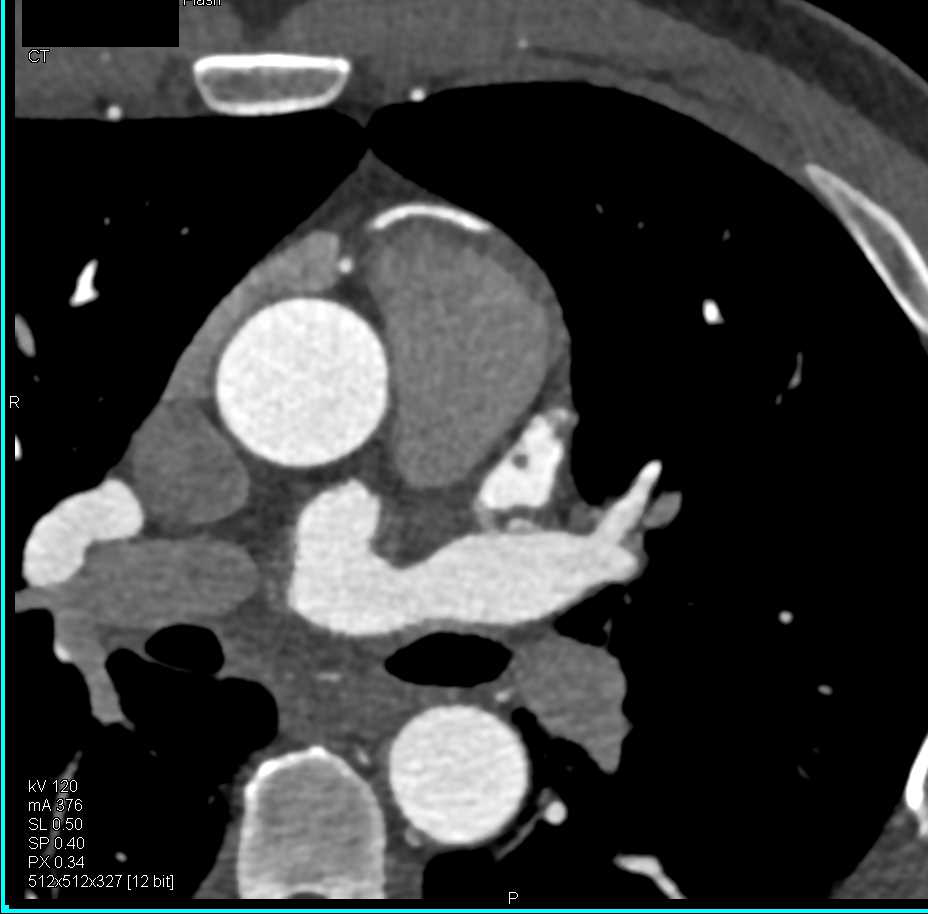

Pseudoaneurysm Aortic Root near Root Repair